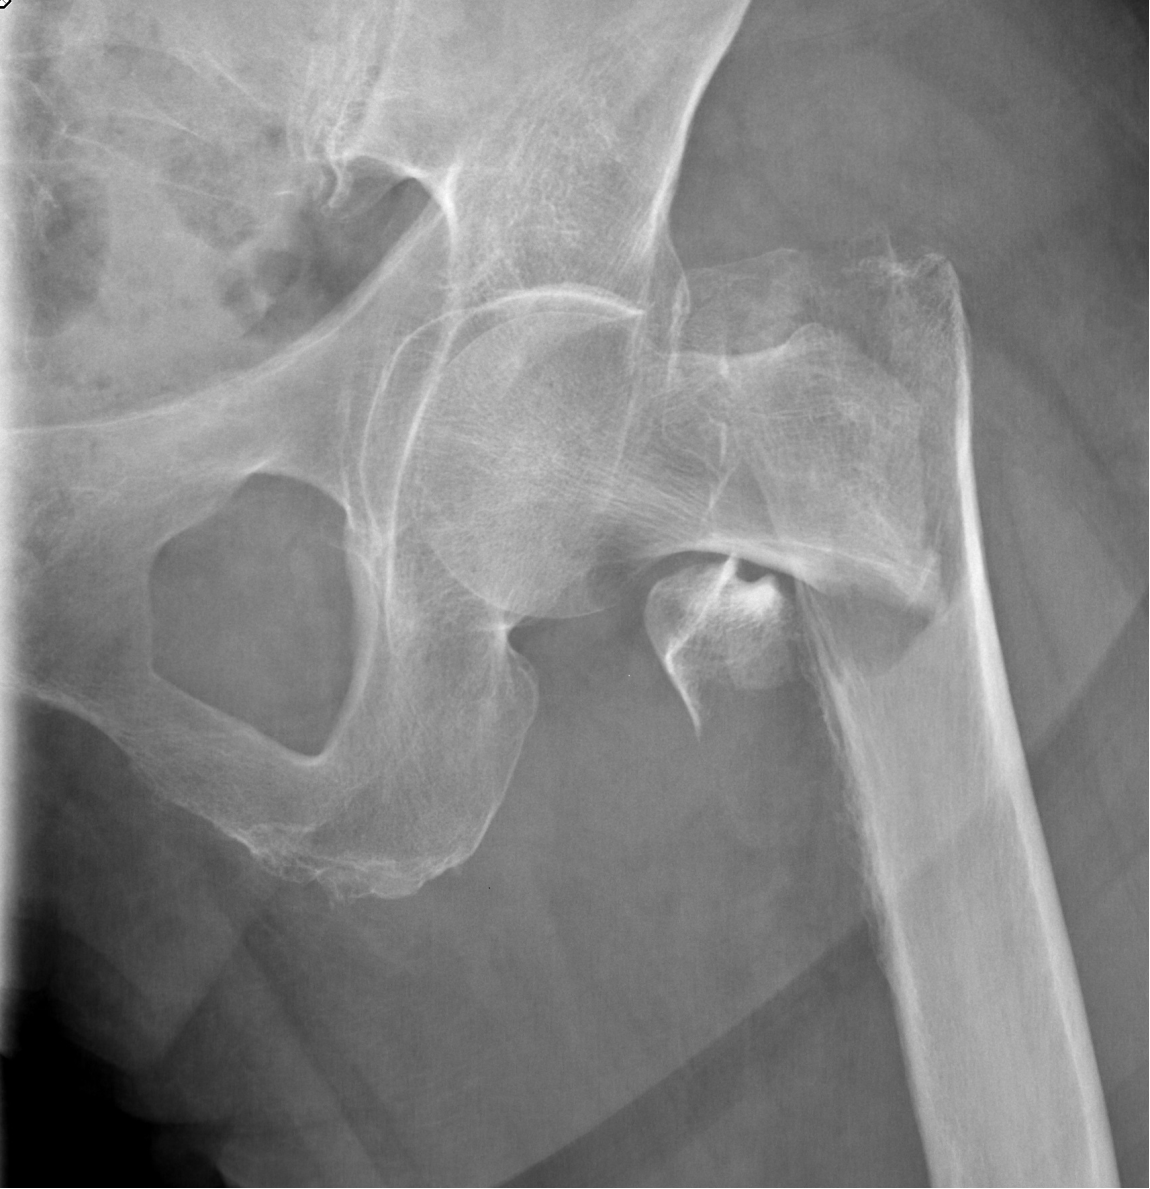

Færre ældre får hoftebrud, men flere får nye hofter på grund af slidgigt.

En ny undersøgelse fra Syddansk Universitet og Københavns Universitetshospital Bispebjerg viser en faldende hyppighed af hoftebrud blandt ældre, men en stigning i hofteoperationer.

Forskerne har fundet en markant nedgang i hoftebrud blandt ældre. Denne positive udvikling skyldes formentlig bedre behandling af knogleskørhed, forebyggelse af fald, øget fysisk aktivitet og færre rygere.

Samtidig med faldet i antal hoftebrud er antallet af hofteoperationer steget, især blandt de ældste.

Nedgang i hoftebrud: - Blandt personer fra 80 til 104 år er hyppigheden af hoftebrud faldet med 35% til 40%.

Stigning i operationer relateret til hoftebrud: - Andelen af personer, der får ny hofte efter et brud, er steget med 50% til 70%. Stigningen er størst hos personer over 75 år.

Stigning i operationer relateret til slidgigt: - Hyppigheden af hofteoperationer udført for at behandle slidgigt hos personer i aldersgruppen 75 til 99 år er steget markant. Stigningen ligger på mellem 60% og 100%, hvilket indikerer næsten en fordobling af hyppigheden af sådanne operationer i denne aldersgruppe over den angivne periode.